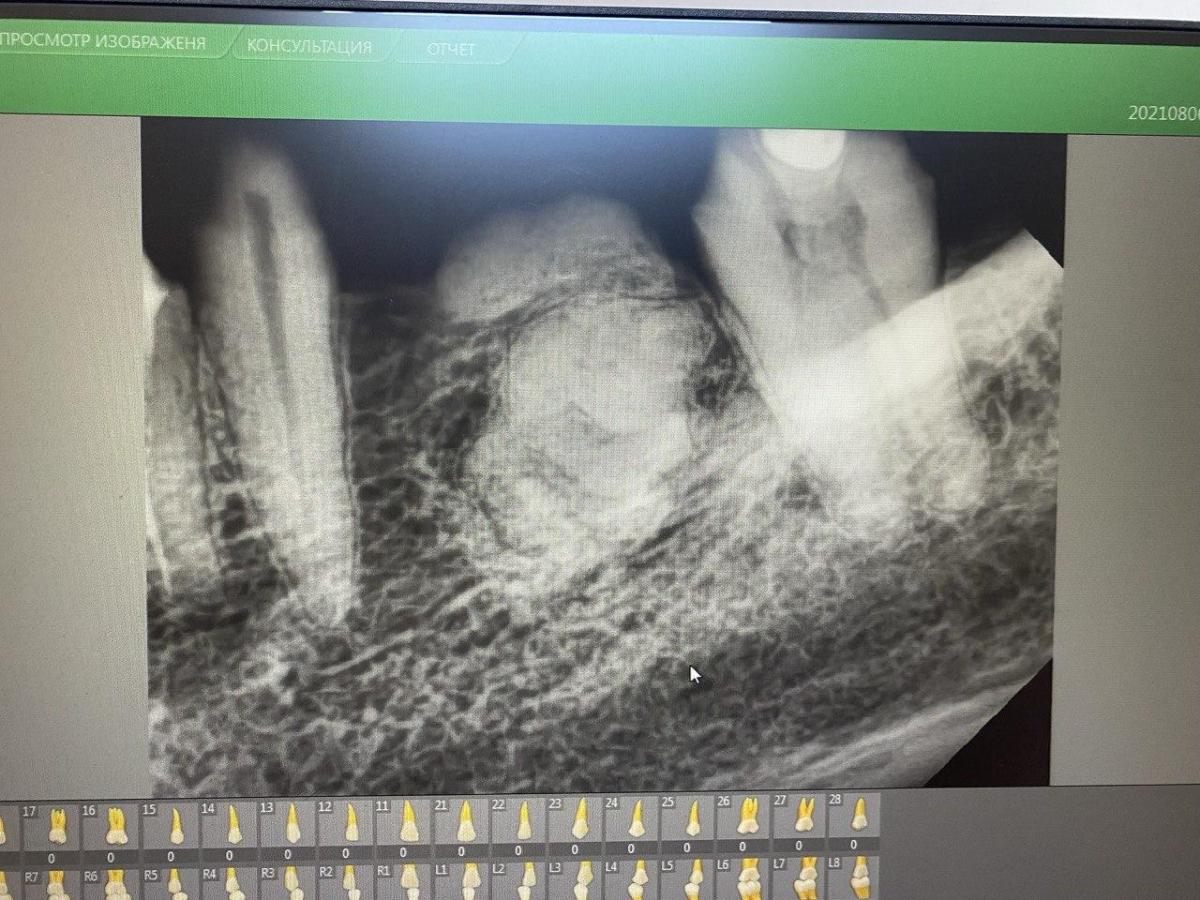

На прицельном снимке определяется образование.

Жалоб нет. Через небольшой дефект слизистой по центру гребня пальпируется плотное округлое образование. Что это может быть и что с этим делать?